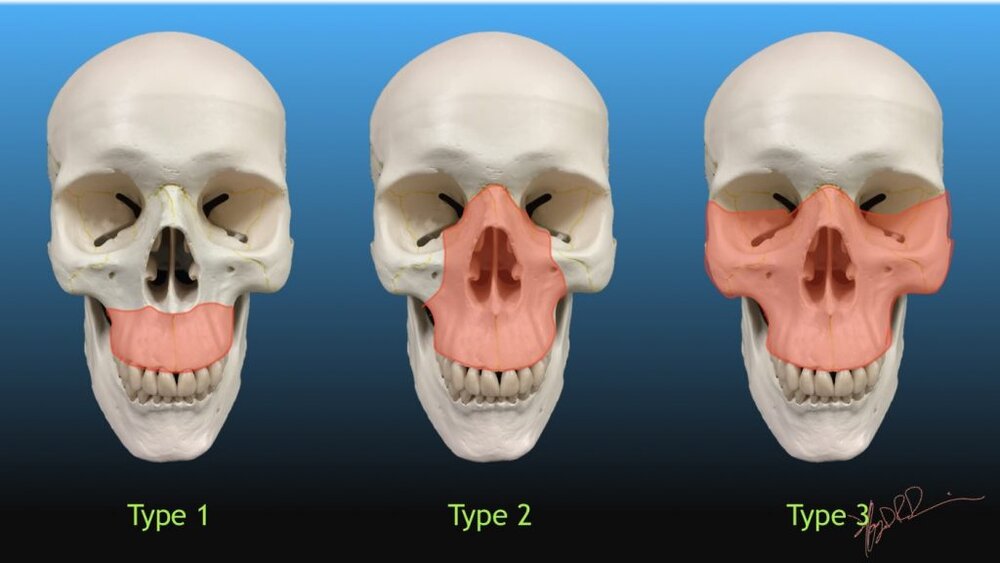

I'm 19. And I'm currently consulting with an Australian maxillofacial surgeon about getting a LeFort I/BSSO+genioplasty and a LeFort III. I believe I'm the most deformed looking Asian person to ever set foot on this site. Every bone of my face lacks forward growth.